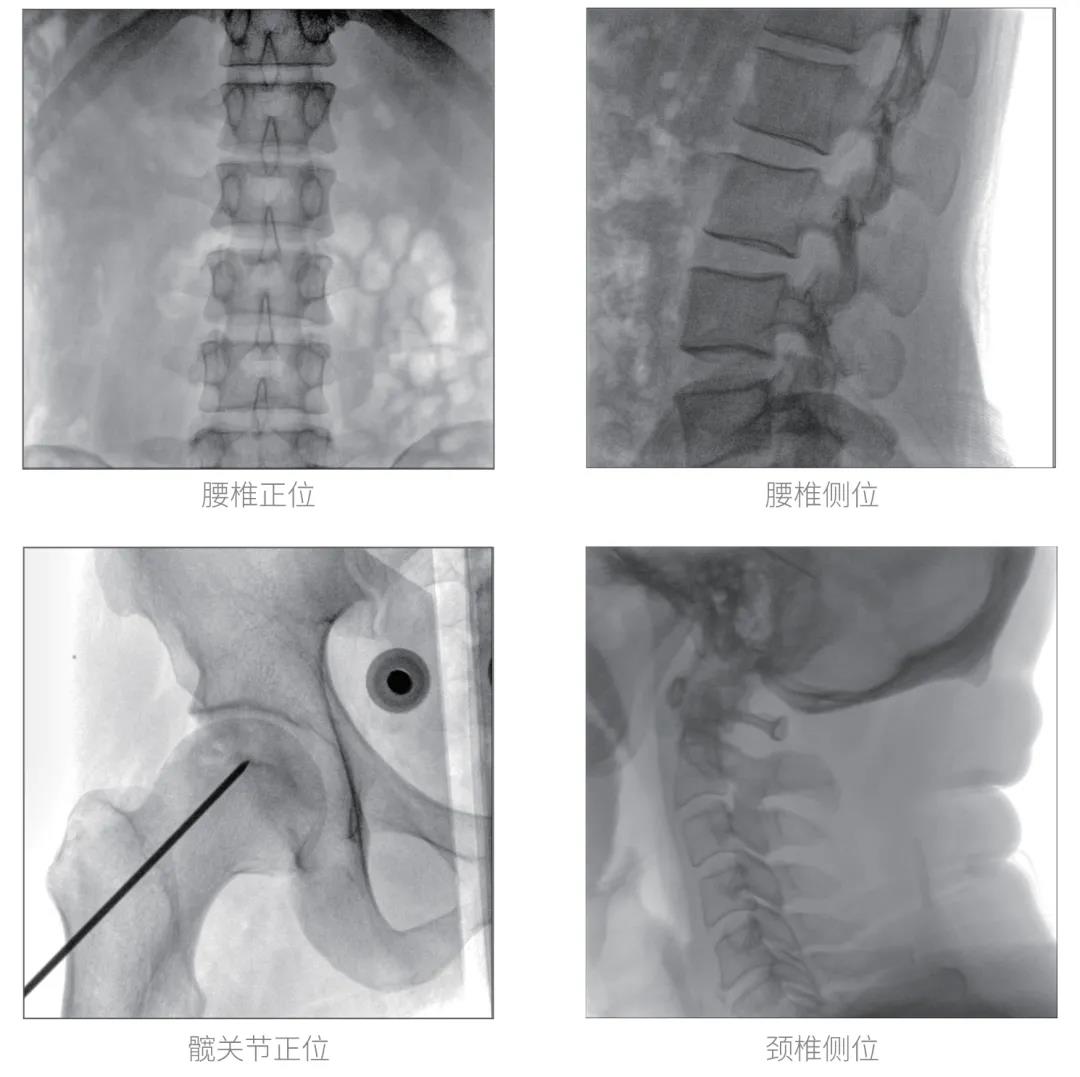

经过认真详尽的设备审核验收,“慧瞳”正式投入使用,普爱医疗一体化平板C形臂采取的动态平板探测器和智能图像处理技术,让临床图像更加清晰。

普爱医疗一体化平板C形臂“慧瞳”采用小巧紧凑的一体化机架设计,配合高性能的动态平板探测器,移动灵活,成像清晰,是各级医院开展骨科及其相关外科手术的科室使用的理想设备。

智能化实时图像处理技术,自动分析图像并进行增强处理,减少临床应用中处理图像时的繁琐操作,快速提供优质图像方便完成临床工作。

根据人体部位与射线剂量自动调整图像帧频,在保证图像质量的同时降低射线剂量。